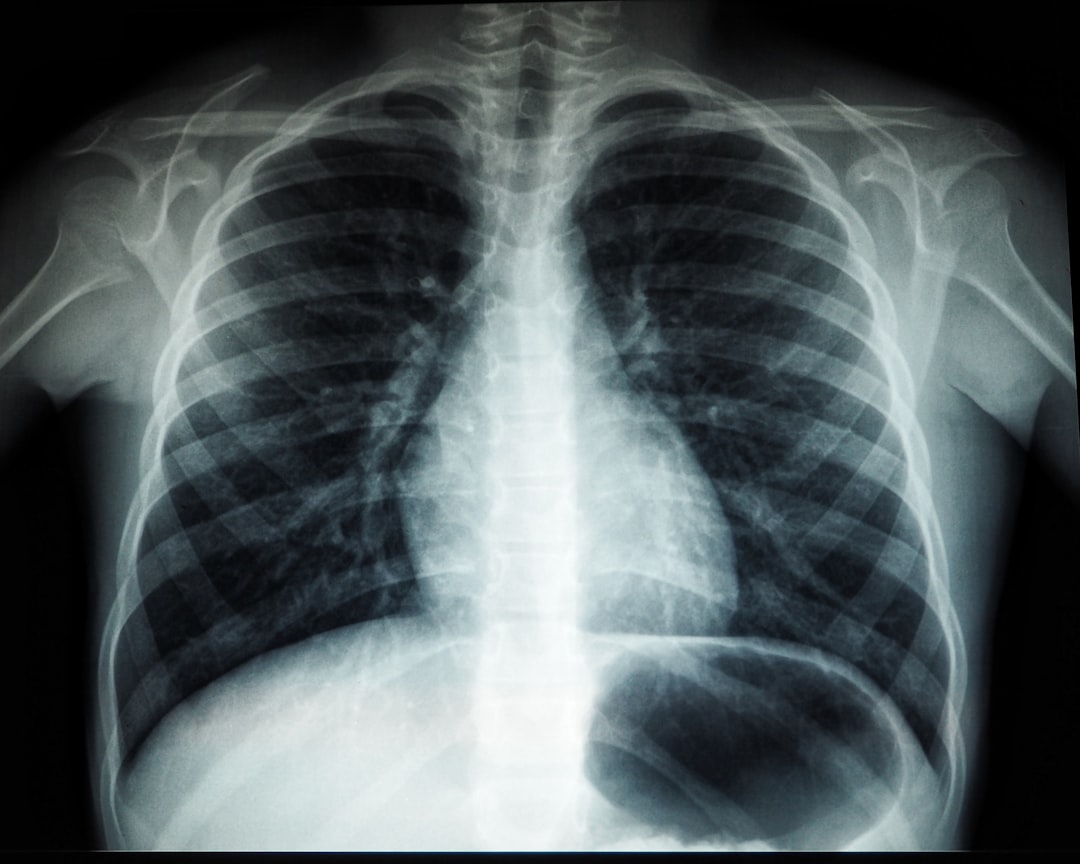

잠복결핵 검사는 특정 집단에 속하는 사람들이 권장됩니다. 예를 들어, 결핵 환자와 밀접하게 접촉한 이들, 이민자, 그리고 결핵 발생률이 높은 지역에서 온 사람들에게 시행되고 있습니다. 이러한 검사는 질병이 확산되는 것을 미연에 방지하기 위함입니다. 그 외에도 면역력이 저하된 환자들, 고위험 군으로 분류되는 환자들도 정기적으로 검사를 받는 것이 좋습니다.

결핵이 활성화되기 전, 아무 증상 없이 잠복 상태일 때 검사가 이루어지기에, 일반 사람들이 자주 생각지 못하는 문제입니다. 하지만 요즘, 여러 매체를 통해 이 검사의 중요성이 점차 강조되고 있습니다. 개인의 건강뿐 아니라, 주변 사람들의 건강을 지키기 위해서라도 잊지 말고 검사를 반드시 받으시길 바랍니다.